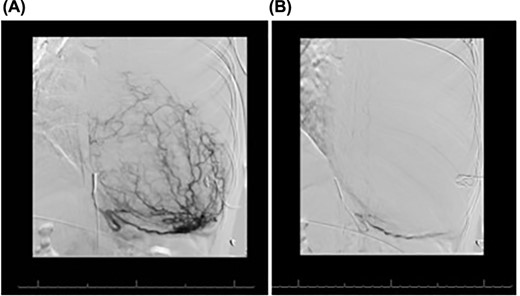

Magnetic resonance imaging showed no invasion of chest wall or visceral structures, consistent with resectability (Fig. 2). To prepare for resection, thoracic aortography showed 75% of tumor arterial supply from left inferior phrenic artery, which was subsequently coiled with particles (500 μm and 700 μm embospheres) (Fig. 3A). Postembolization arteriogram demonstrated near complete cessation of anterior flow within this vessel and its branches (Fig. 3B).

Coronal magnetic resonance image, showing the large heterogeneous mass occupying the left hemithorax. Note severe displacement of the heart and vasculature as well as complete atelectasis of the lung (L), left ventricle (LV), right atrium (RA), aorta (A), pulmonary trunk (P).